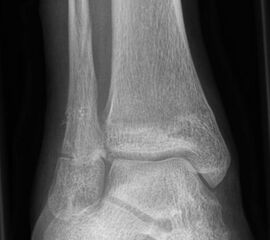

Fugengelenkfrakturen treten typischerweise vor dem 10. Lebensjahr auf, in einer Phase, in welcher die Wachstumsfugen noch weit offen sind. Dieser Frakturtyp betrifft fast ausschließlich den medialen Malleolus. Laterale Frakturen sind extrem selten, teilweise kommt es zu lateralen Bandverletzungen oder Fugenschaftfrakturen der distalen Fibula. Die Frakturlinie verläuft in einer Verlängerungslinie von der medialen Taluskante nach proximal. Häufig stellen sich Verletzungen des Innenknöchels im Röntgenbild schlechter dar, insbesondere wenn die Aufnahmen verdreht sind oder die Ebene der Fraktur bei geringer Dislokation verkippt zur Röntgenebene liegt. Besteht klinisch der geringste Hinweis auf eine Verletzung des Innenknöchels, muss aufgrund der Tragweite der Verletzung durch entsprechende Aufnahmen gegebenenfalls auch Schnittbildverfahren die Verletzung sicher diagnostiziert oder ausgeschlossen werden (Abb. 15).

Fugengelenkfrakturen können die Wachstumsfuge durchkreuzen (Abbildung 16a), ohne oder nur mit minimaler Beteiligung der Fuge sehr weit medial liegen (Abbildung 16b) oder durch die Fuge auslaufen (Abbildung 16c). Relevant für die Wachstumsprognose ist weniger die Form der Fraktur, sondern das Alter des Patienten zum Zeitpunkt des Traumas sowie das Ausmaß der Schädigung der Wachstumsfuge, wobei eine Korrelation mit dem Ausmaß der Dislokation besteht.